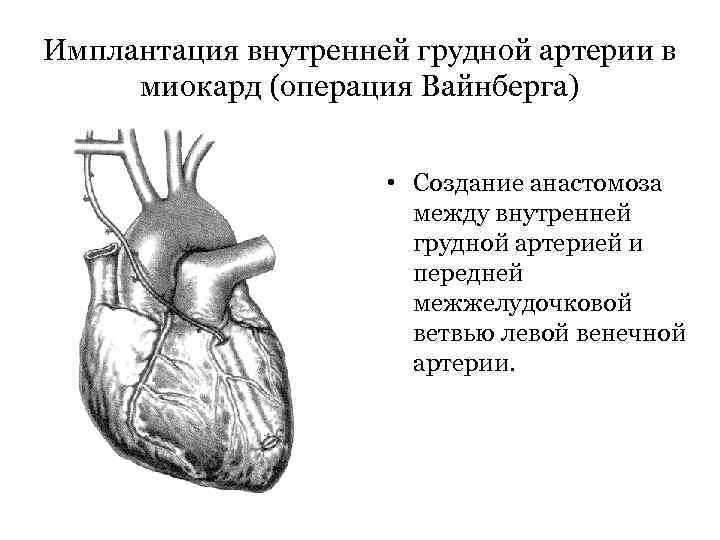

Имплантация внутренней грудной артерии в миокард (операция Вайнберга) • Создание анастомоза между внутренней грудной артерией и передней межжелудочковой ветвью левой венечной артерии.

Имплантация внутренней грудной артерии в миокард (операция Вайнберга) • Создание анастомоза между внутренней грудной артерией и передней межжелудочковой ветвью левой венечной артерии.